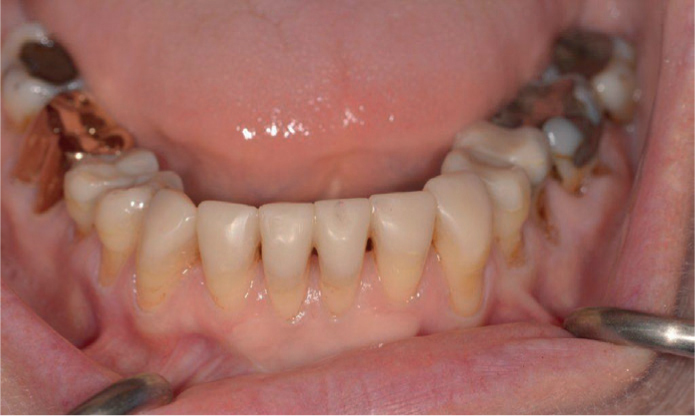

Composite veneers are a cosmetic dental solution designed to restore the appearance and function of teeth with damaged or missing edges. They are crafted from a tooth-colored resin material that can be carefully shaped and bonded to the natural tooth surface. This method offers an immediate improvement in appearance while maintaining a natural look and feel.

Composite Veneers in Dubai are favored for their versatility and ability to address a variety of dental imperfections, including chips, cracks, and uneven tooth edges. They provide a seamless way to rebuild teeth while preserving the natural enamel.

Composite veneers are suitable for individuals with minor chips, cracks, or missing edges on their teeth. They are particularly effective for repairing front teeth where aesthetic appearance is a priority.

Candidates should have good oral hygiene and healthy teeth and gums. Composite veneers are not ideal for teeth with extensive decay or severe structural damage, as alternative treatments may be more appropriate.